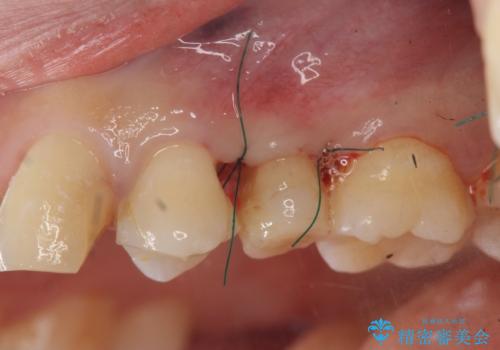

- 歯ぐきの腫れや、歯の内部が黒く見えることからの虫歯の治療を求めて来院されました。

虫歯が大きかったことから、神経の温存はできたものの歯ぐきよりも深い虫歯の問題を解決するため、部分矯正治療を併用したセラミック治療を行うこととしました。

当初、歯ぐきよりも深い虫歯の存在や、歯のポジションに問題がありましたがマルチブラケットを用いた部分矯正で行うことで歯の挺出同時に適切な位置へと歯を移動させ、歯周環境を整えたセラミック治療を行うことができました。